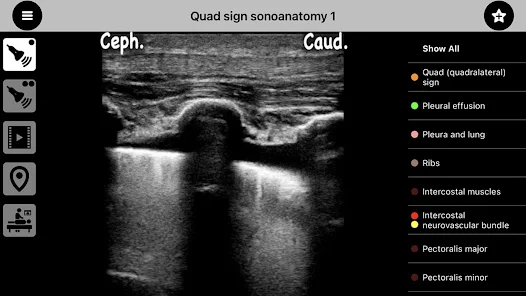

"AnSo Anaesthesia Sonoanatomy" es una innovadora aplicación diseñada para profesionales de la anestesia y la medicina. Ofrece una guía interactiva de la anatomía sonográfica, facilitando el aprendizaje y la práctica de técnicas de anestesia regional. Con imágenes detalladas y descripciones claras, los usuarios pueden mejorar su comprensión de la anatomía relevante y optimizar sus habilidades clínicas. Ideal para estudiantes y médicos, "AnSo" es una herramienta esencial para el éxito en el campo de la anestesiología.

"AnSo Anaesthesia Sonoanatomy" es una innovadora aplicación móvil diseñada específicamente para profesionales de la anestesiología y la medicina. Esta herramienta se centra en proporcionar una comprensión profunda de la anatomía sonográfica, facilitando el aprendizaje y la práctica de técnicas de anestesia regional. Con una interfaz intuitiva y recursos educativos de alta calidad, "AnSo" se convierte en un aliado indispensable para anestesistas, residentes y estudiantes de medicina.

• Imágenes de alta resolución: La aplicación ofrece imágenes sonográficas de alta calidad que permiten a los usuarios visualizar la anatomía de manera clara y detallada.